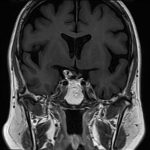

断層撮影

手術前1